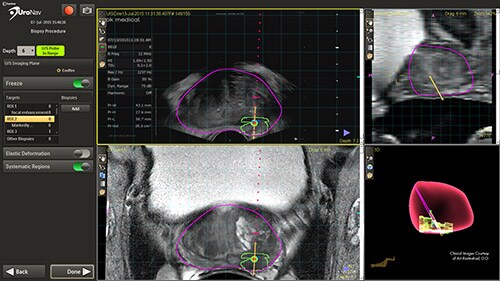

UroNav is an image-guided stereotactic biopsy system used to detect prostate cancer within patients as an alternative to current blind or blind systematic biopsies. It uses multi- parametric magnetic resonance (mpMR) imaging, fused with live ultrasound (US) guidance in conjunction with electromagnetic (EM) tracking to plan, guide, and document prostate biopsies. UroNav simultaneously displays registered MR and ultrasound images and the projected needle path relative to the suspicious target lesion during the biopsy procedure and guides the urologist in real-time.

This novel approach has the ability to improve the sensitivity and specificity of prostate biopsies. This results in a reduced incidence rate of false negative biopsy results. Conventional biopsy or “blind” procedures have a far lower cancer detection rate, which affects patient outcomes by delaying diagnosis, treatment intervention, and limiting treatment options. By enabling earlier diagnosis, UroNav allows a broader array of treatment options to be considered by the clinician, less complications for the patient, and a more cost-effective resolution for the care provider. From set up to post-biopsy review, UroNav guides you through its intuitive workflow. After a quick initialization of the navigation system (upper image), UroNav creates a 3D ultrasound volume from a standard 2D scan of the prostate (lower image).